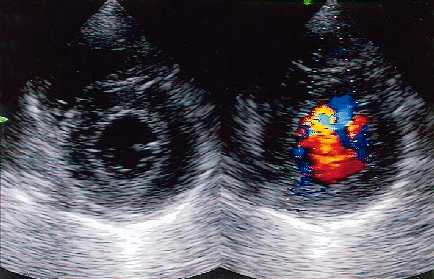

Modo M: Se utiliza para estudiar movimientos de órganos, especialmente del corazón (ecocardiogramas). Un registro de tiempo-posición representa cómo varía una línea de eco A en función del tiempo.

Técnicas Doppler: Cuando el haz sonoro rebota en una superficie inmóvil, la frecuencia del haz reflejado es la misma que la del haz transmitido, pero si la superficie se mueve, el ultrasonido reflejado tendrá diferente frecuencia que el emitido (efecto Doppler). Esto se puede analizar para estudiar dicho movimiento.

Veamos algunas ecografías a modo de ilustración:

Ecocardiografía Doppler                                           Ecografía de ovarios